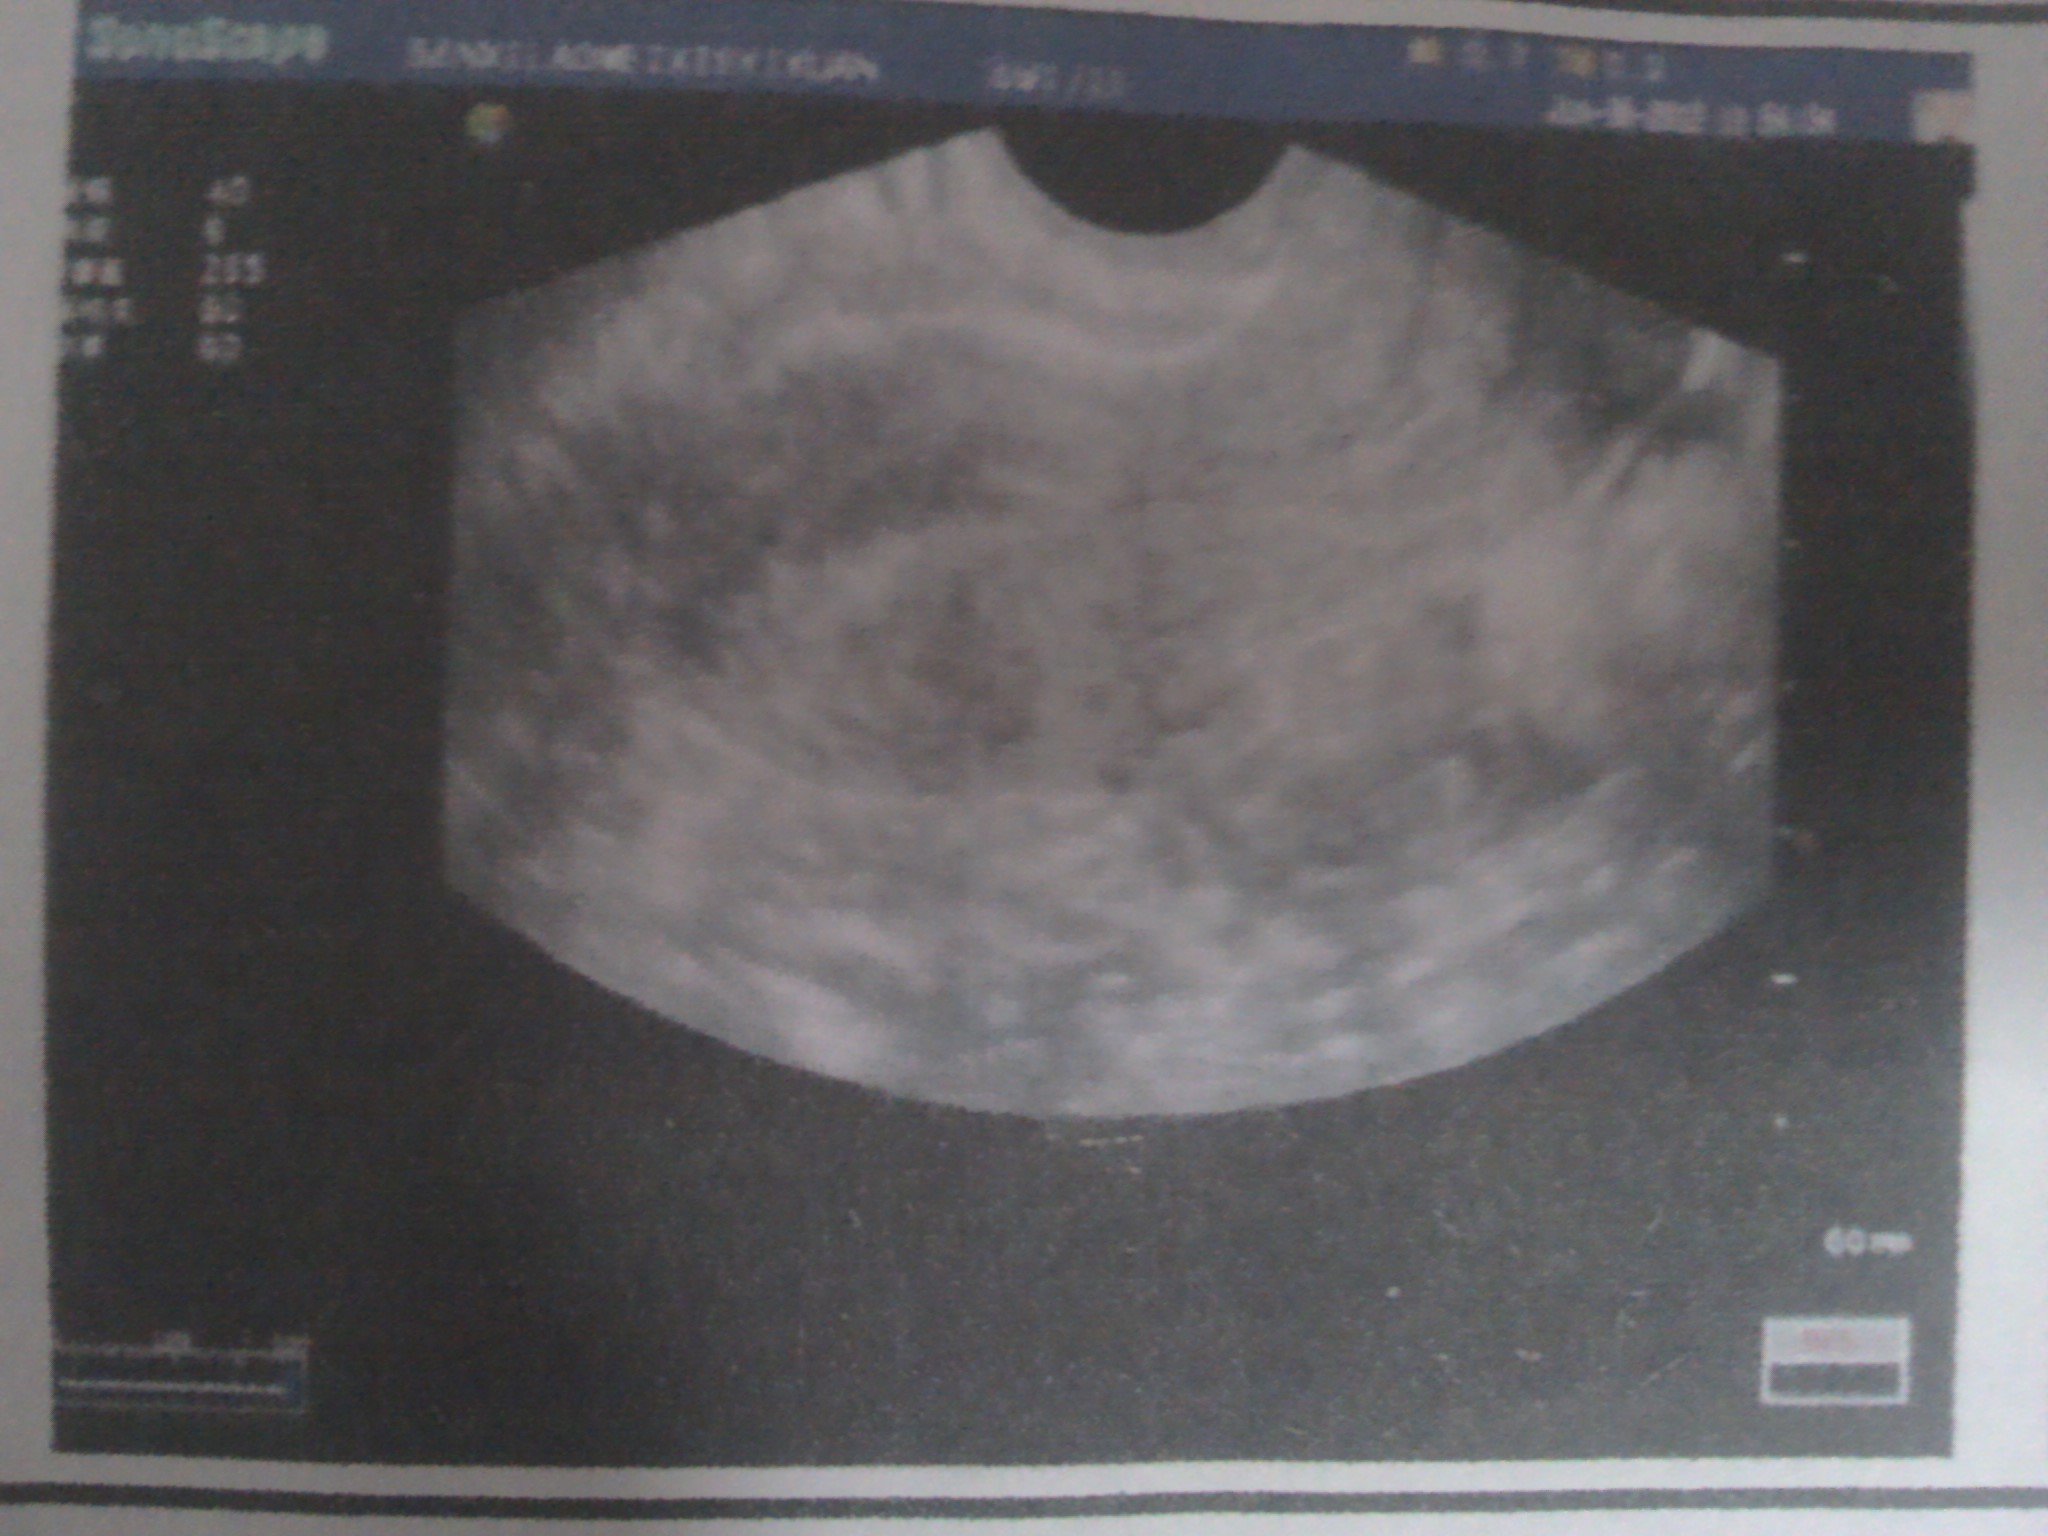

患者信息:女 31岁 辽宁 本溪 病情描述(发病时间、主要症状等):图1,图2,图3,是2012年6月30日拍的。超声所见:子宫前位,大小约4.6*3.6*3.6cm,肌层回声均匀。内膜厚约0.6cm。 左侧卵巢大小约2.5*2.1cm,内见2.4*2.0囊性暗区。 右侧卵巢大小约3.8*3.7cm囊性暗区,囊壁光滑,囊液透气好。诊断意见:左卵巢囊性结构,右卵巢囊肿—————————————————————————————————图4,图5,图6 是2012年9月25日拍的超声描述:子宫体大小约:3.8*3.9*2.8cm 子宫前位,轮廓清晰,光滑,肌层回声均匀,内膜厚约0.6cm 左卵巢大小约:3.2*1.6cm,右卵巢大小约:2.6*1.8cm,双附件区均可见无回声团,形态不规则,大小分别约5.8*2.9*3.5cm(左侧),6.2*3.2*3.4cm(右侧) 宫颈厚约2.2cm,回声较均匀。超声提示:双侧附件区囊性包快(考虑输卵管积液)想得到怎样的帮助:未婚,打算要孩子。这两次检查相差三个月,之前检查,都没说有输卵管积液。这次医生态度很严肃,说输卵管造影和通水现在都没用了。让我做腹腔镜,考虑试管婴儿。我的情况非常严重吗?怎么治疗?能看出我是哪种囊肿吗曾经治疗情况及是否有过敏、遗传病史:没治疗过。